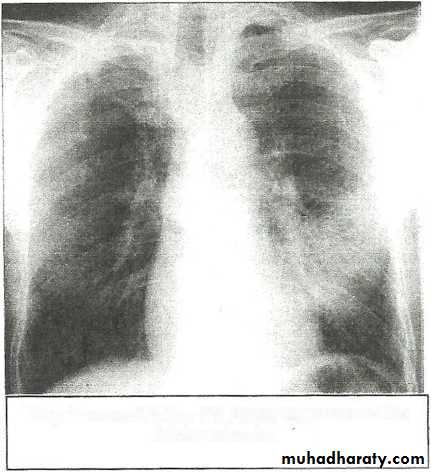

Mycoplasma pneumonia. A 35 year old man presents with nonproductive cough and fever